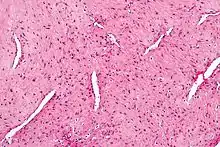

| Micrograph of a nasopharyngeal angiofibroma H&E stain. | |